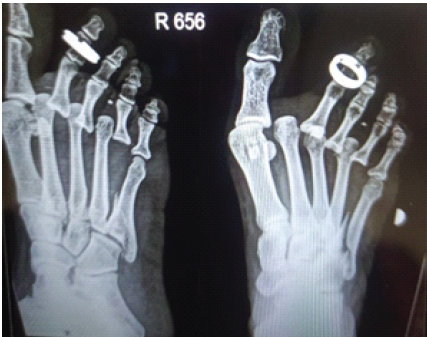

Plain radiographs of the right foot showed dorsolateral dislocation of the 2nd, 3rd, and 4th MTP joints and an oblique intra-articular fracture of the 5th metatarsal base (Fig. 2).

Figure 2: X-ray of right foot showing dorsolateral dislocation of 2nd, 3rd, and 4th metatarsophalangeal joints.

Figure 4: X-ray of right foot showing stable metatarsophalangeal joints post-closed reduction.

Figure 5: X-ray of right foot showing stable metatarsophalangeal joints with complete union of the base of the 5th metatarsal fracture.